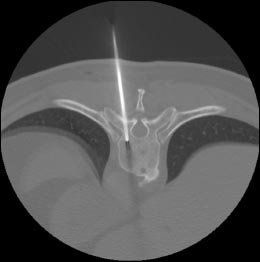

FIGURE 2OnControl needle in the CT-targeted vertebral body (

top

). Post-biopsy at same vertebral body showing the resultant bone channel after removal of bone plug specimen (

bottom

). Images courtesy of Dr. Symington.